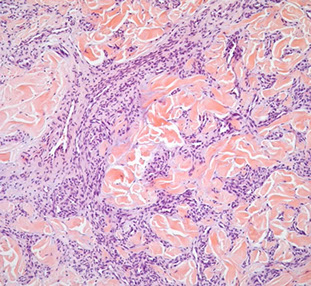

Kaposi sarcoma

Kaposi sarcoma - early patch stage

Kaposi sarcoma, nodular stage